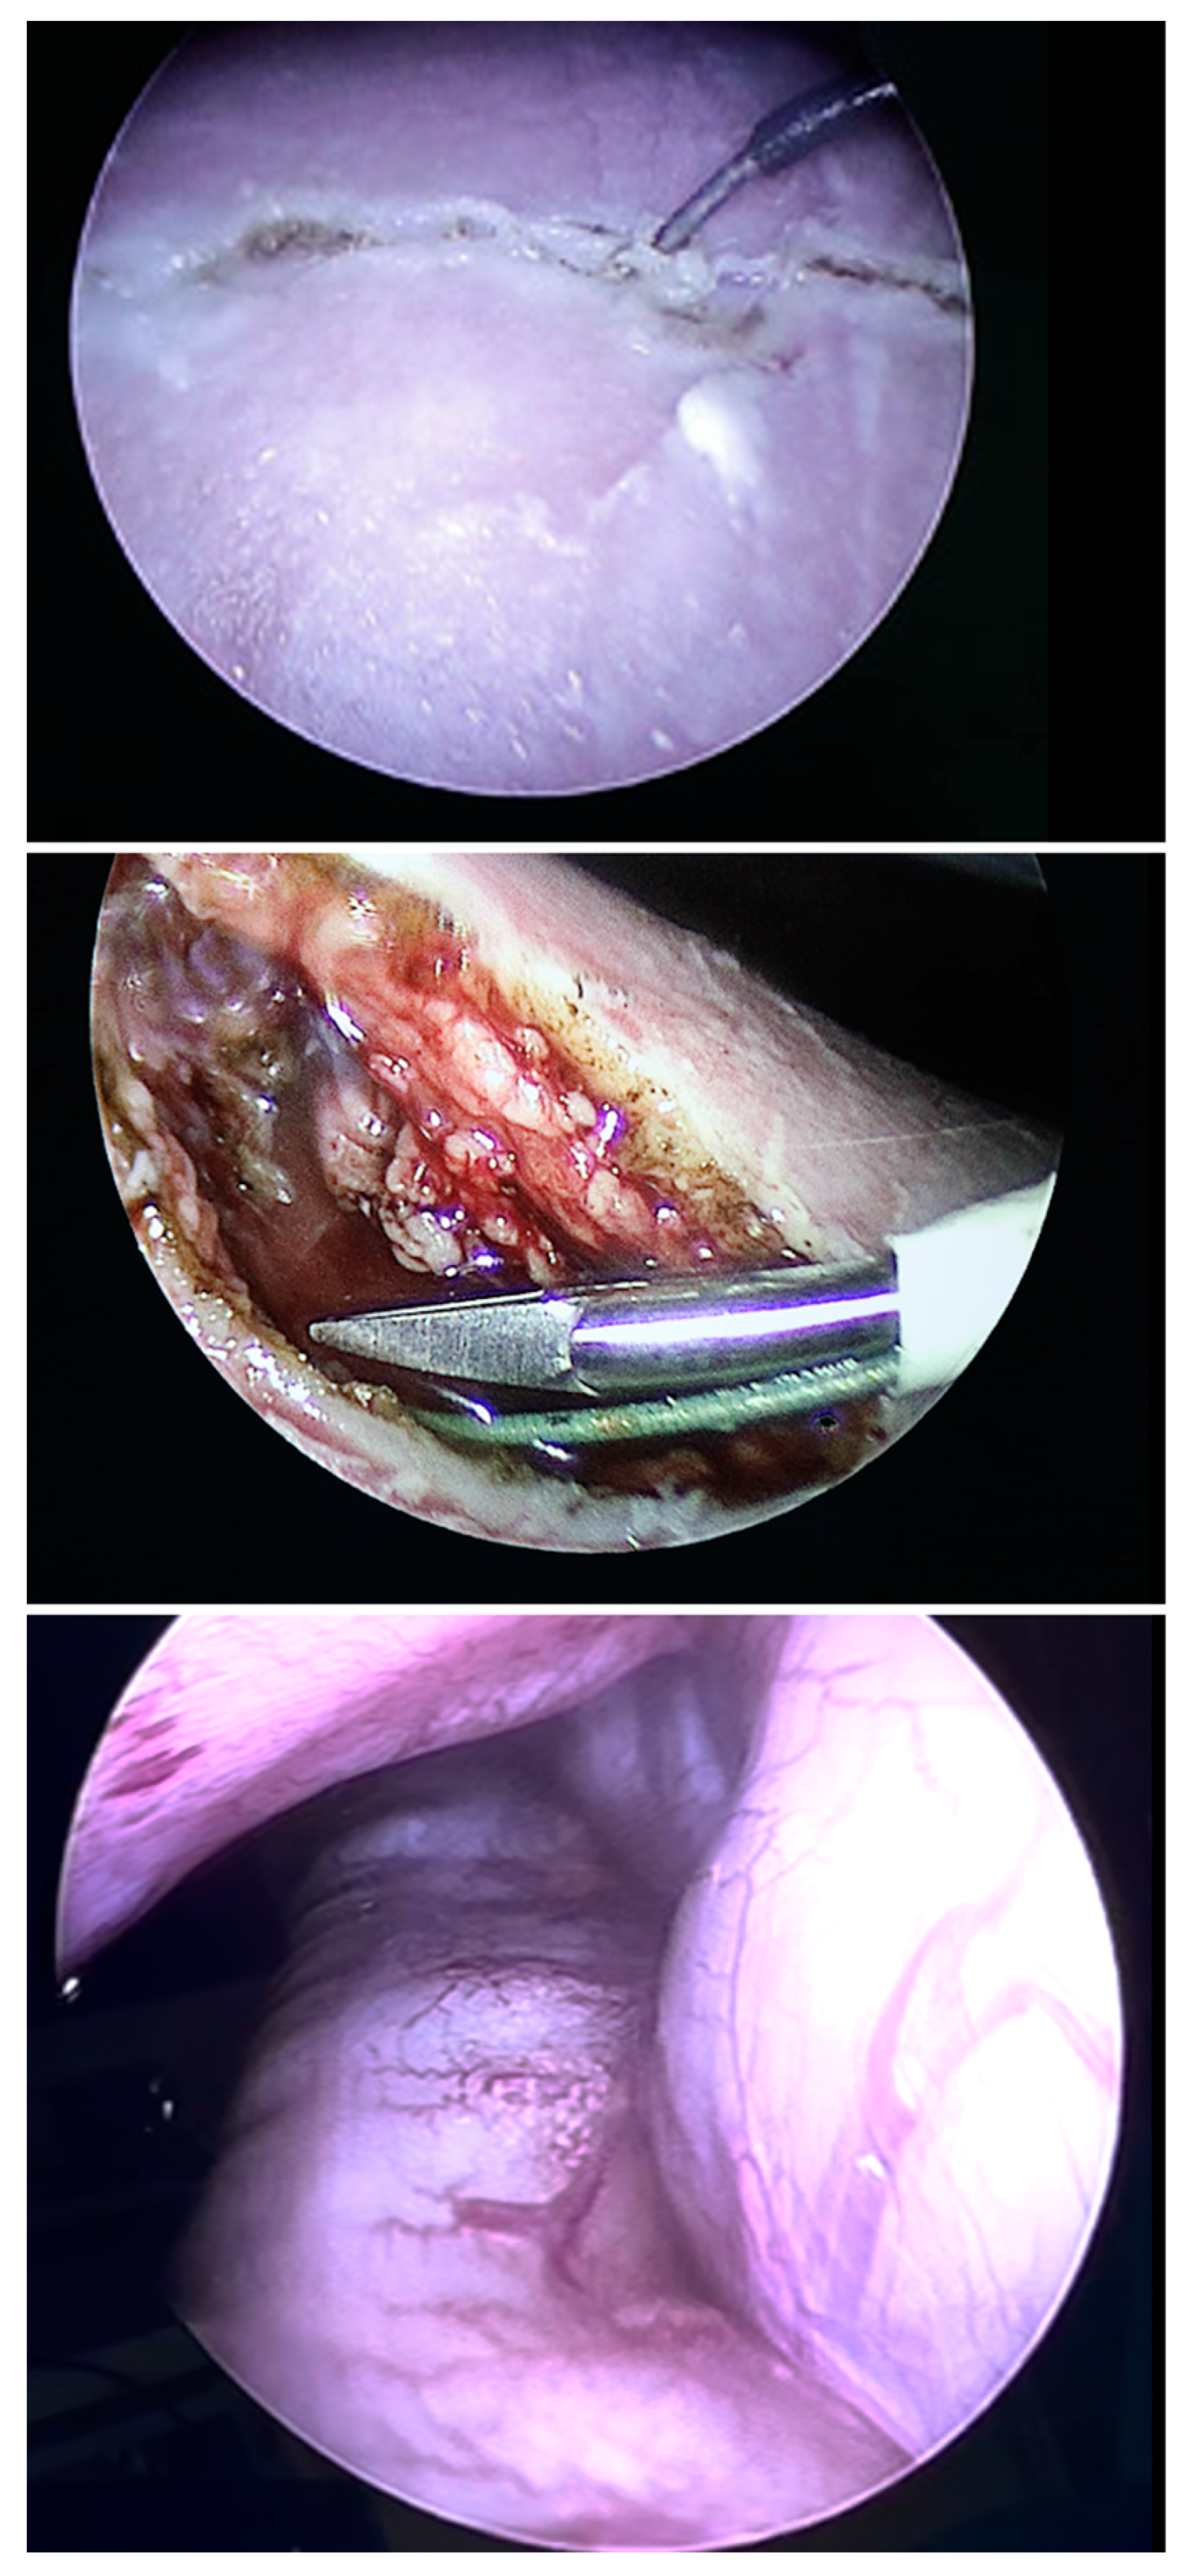

Case Report: Fetoscopic Laparoschisis (FETO-LAP)—A New Therapeutic Route to Explore for Fetuses with Severe Diaphragmatic Hernias

Case